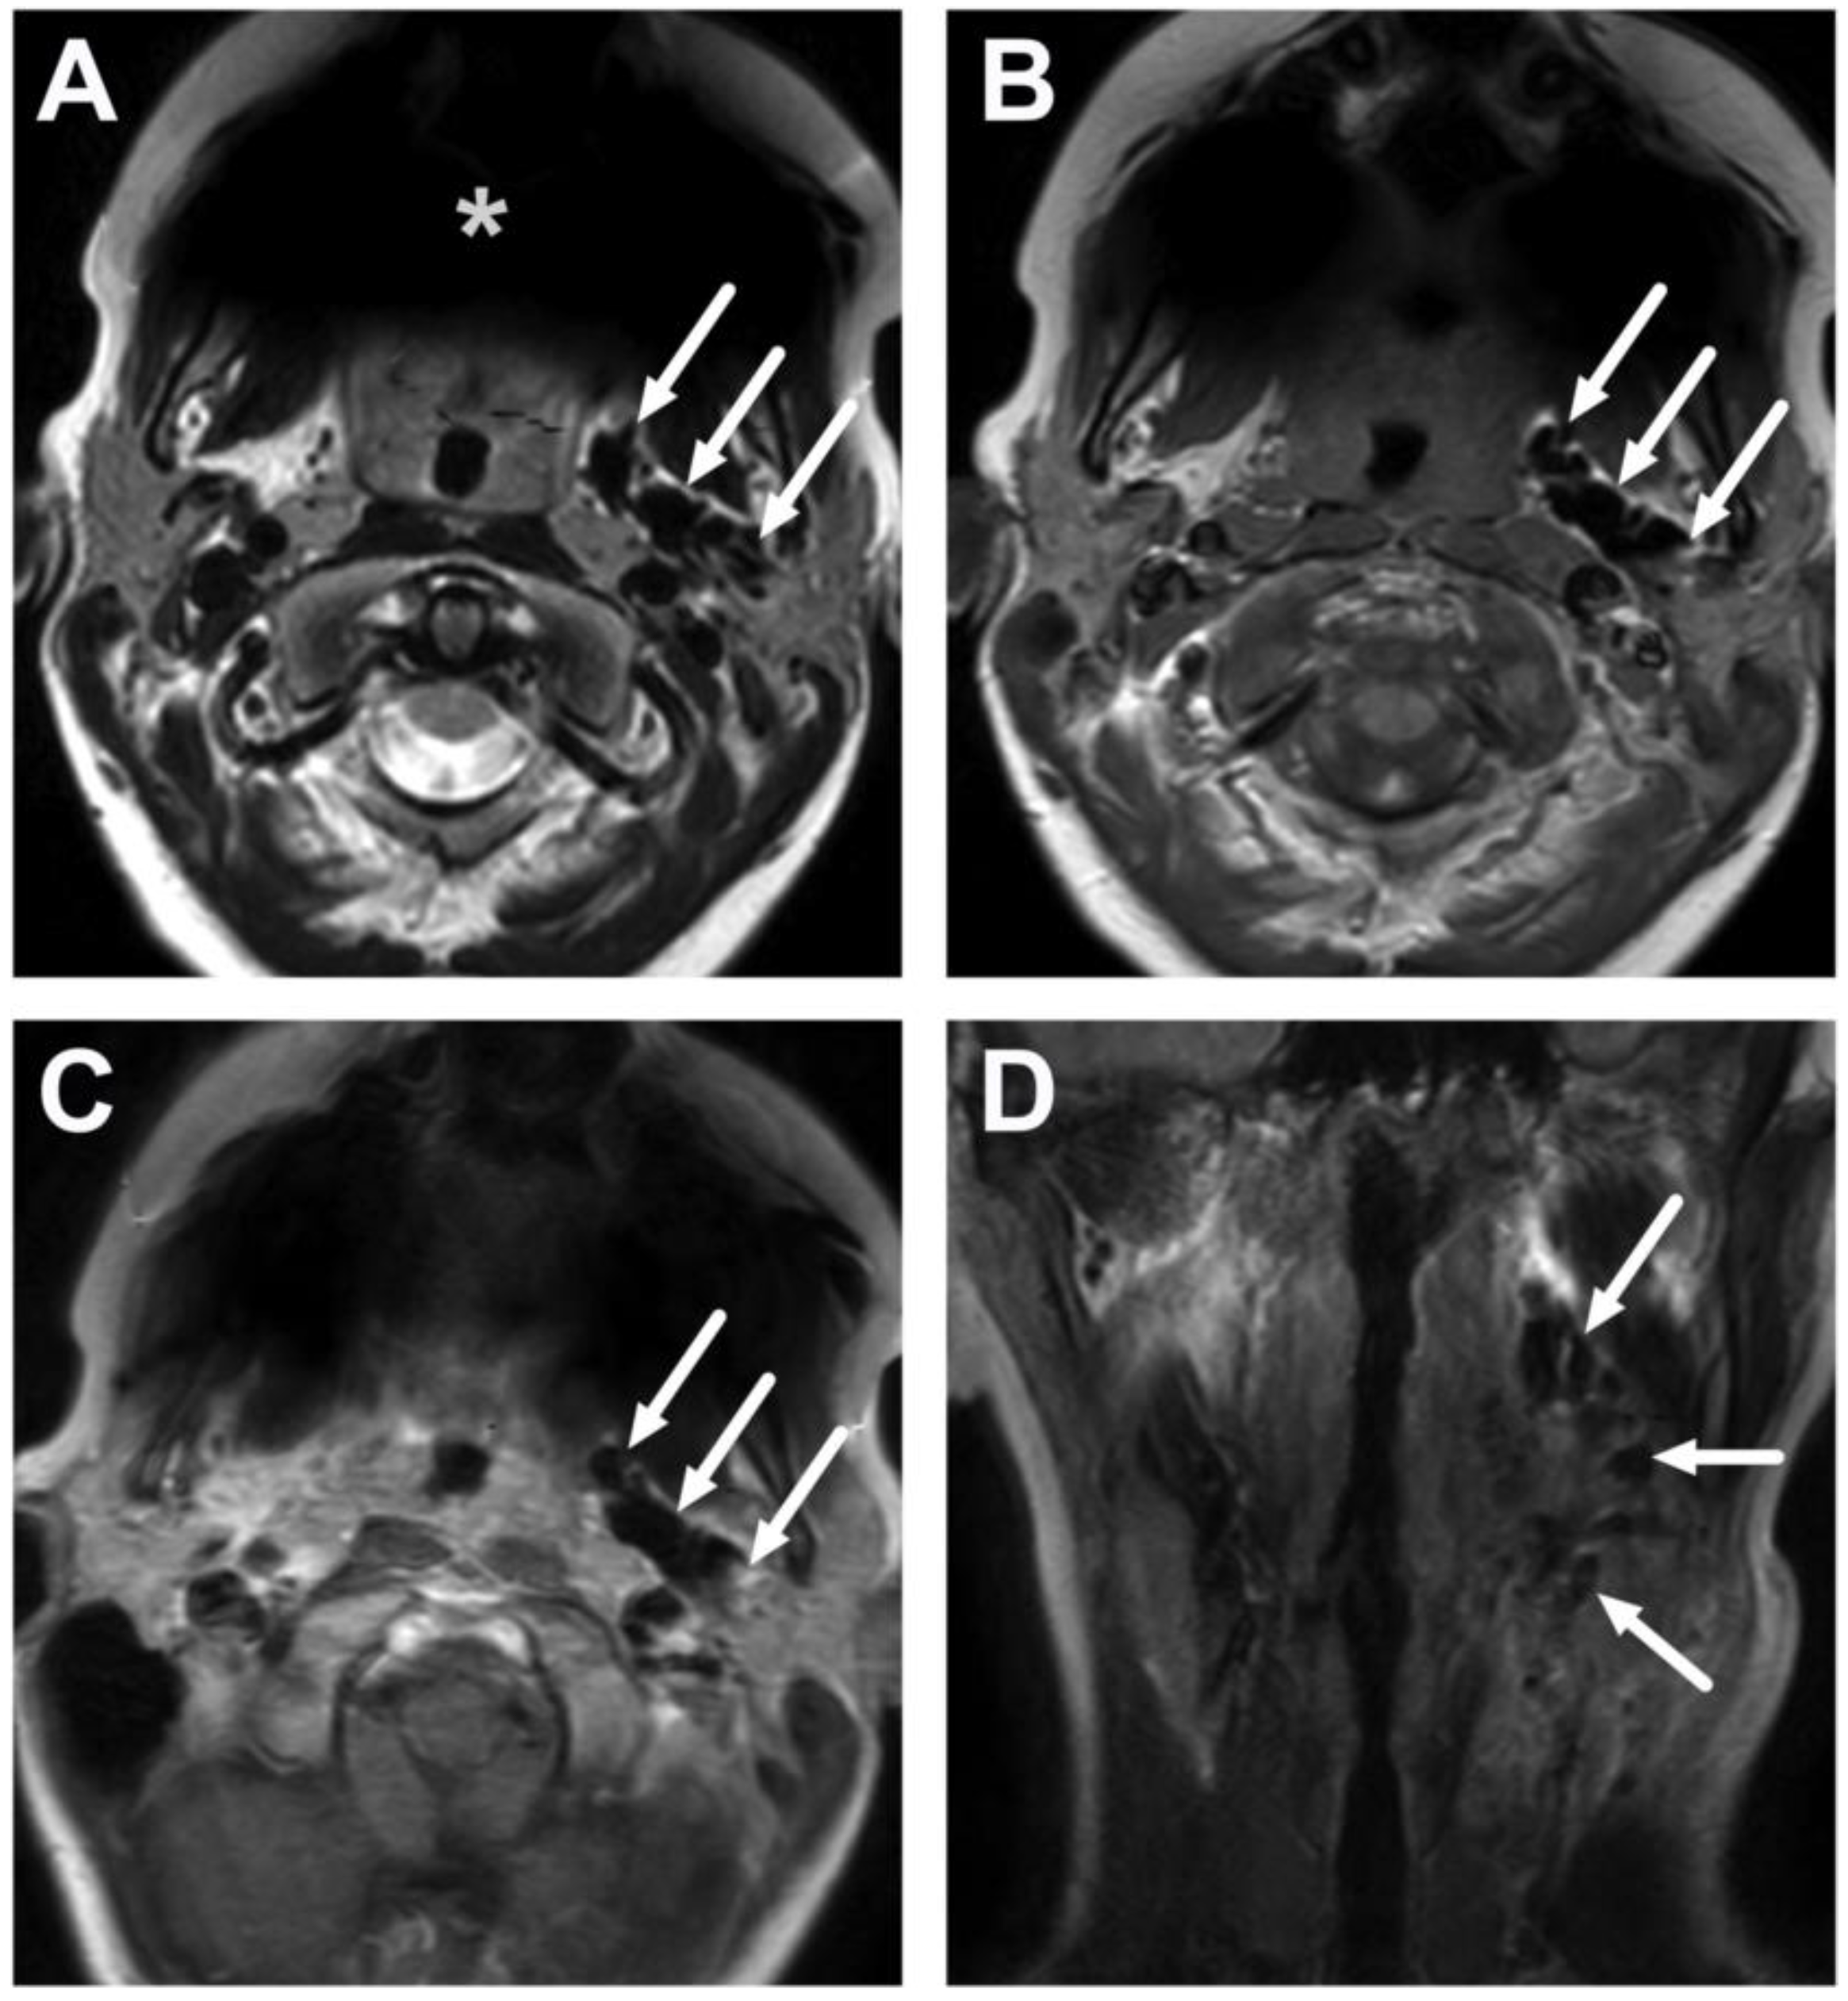

4.1. Tonsillitis, Peritonsillar Abscesses, and Parapharyngeal Abscesses

4.2. Retropharyngeal Abscesses and Suppurative Lymphadenitis

4.3. Oral Cavity